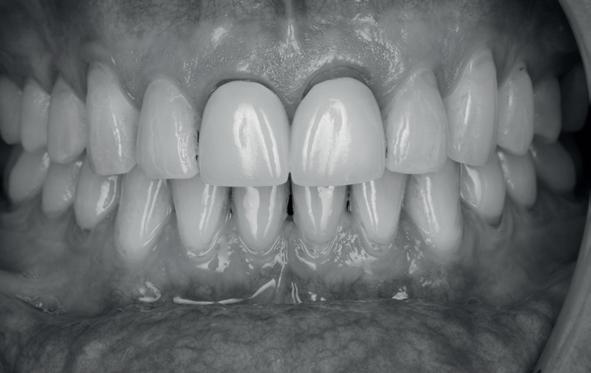

Esthetiek in de tandheelkunde, met name in het front, is een samenspel tussen de roze zachte weefsels en de witte harde weefsels. In het Engels wordt dit ook wel aangeduid met “pink and white esthetics”, waarbij het verkrijgen van correcte pink esthetics over het algemeen een grotere uitdaging vormt dan de white esthetics. Deze roze esthetiek is vooral van belang bij gebitselementen waarbij sprake is van recessie (het terugtrekken van de gingivalijn, waardoor de radix en een langere tand zichtbaar worden). De situatie wordt nog uitdagender wanneer een tand of kies niet is aangelegd, of in het verleden is verwijderd. Het element zorgt er immers voor dat de gingiva rondom de natuurlijke kroon ligt en dat er voldoende weefseldikte rondom deze kroon aanwezig is. Als het element ontbreekt, groeit het alveolaire bot dicht, omdat er geen radix meer is, en daarmee ook de mucosa (wanneer er geen element meer aanwezig is, spreken we niet meer van gingiva maar van mucosa), die dan afgevlakt is. De papillen tussen de afwezige elementen vlakken dan ook af.

Om één of meer afwezige elementen te herstellen bij een vaste voorziening, kan er een etsbrug of kunnen er implantaten worden geplaatst. De esthetiek valt of staat hierbij met de aanvulling van de zachte weefsels, zowel in de vorm van verbreding hiervan als het creëren van een zogenoemd emergence profile –dat wil zeggen dat de tand op een natuurlijk ogende wijze vanuit het tandvlees tevoorschijn moet komen.

tinaal geslepen te worden als er geen 1,5 mm ruimte voor de vleugels behaald kan worden. De ruimte was op de dunste plekken 1 mm, dus een kleine preparatie in de 12 en 22 palatinaal was nodig. Omdat de kaak volledig afgevlakt was en dun was geworden, kunnen de dummies van de etsbrug enkel op de kaak “gelegd worden”, maar daarbij zijn er geen papillen en staat de cervicale rand van de dummies net voor de kaak. Een esthetisch resultaat kan daarmee niet behaald worden. Daarom is een aanvulling van de zachte weefsels in de breedte nodig, als het creëren van een emergence profile, waarbij het oogst alsof de gebitselementen uit het weefsel vertrekken.

5. Beginsituatie voor behandeling